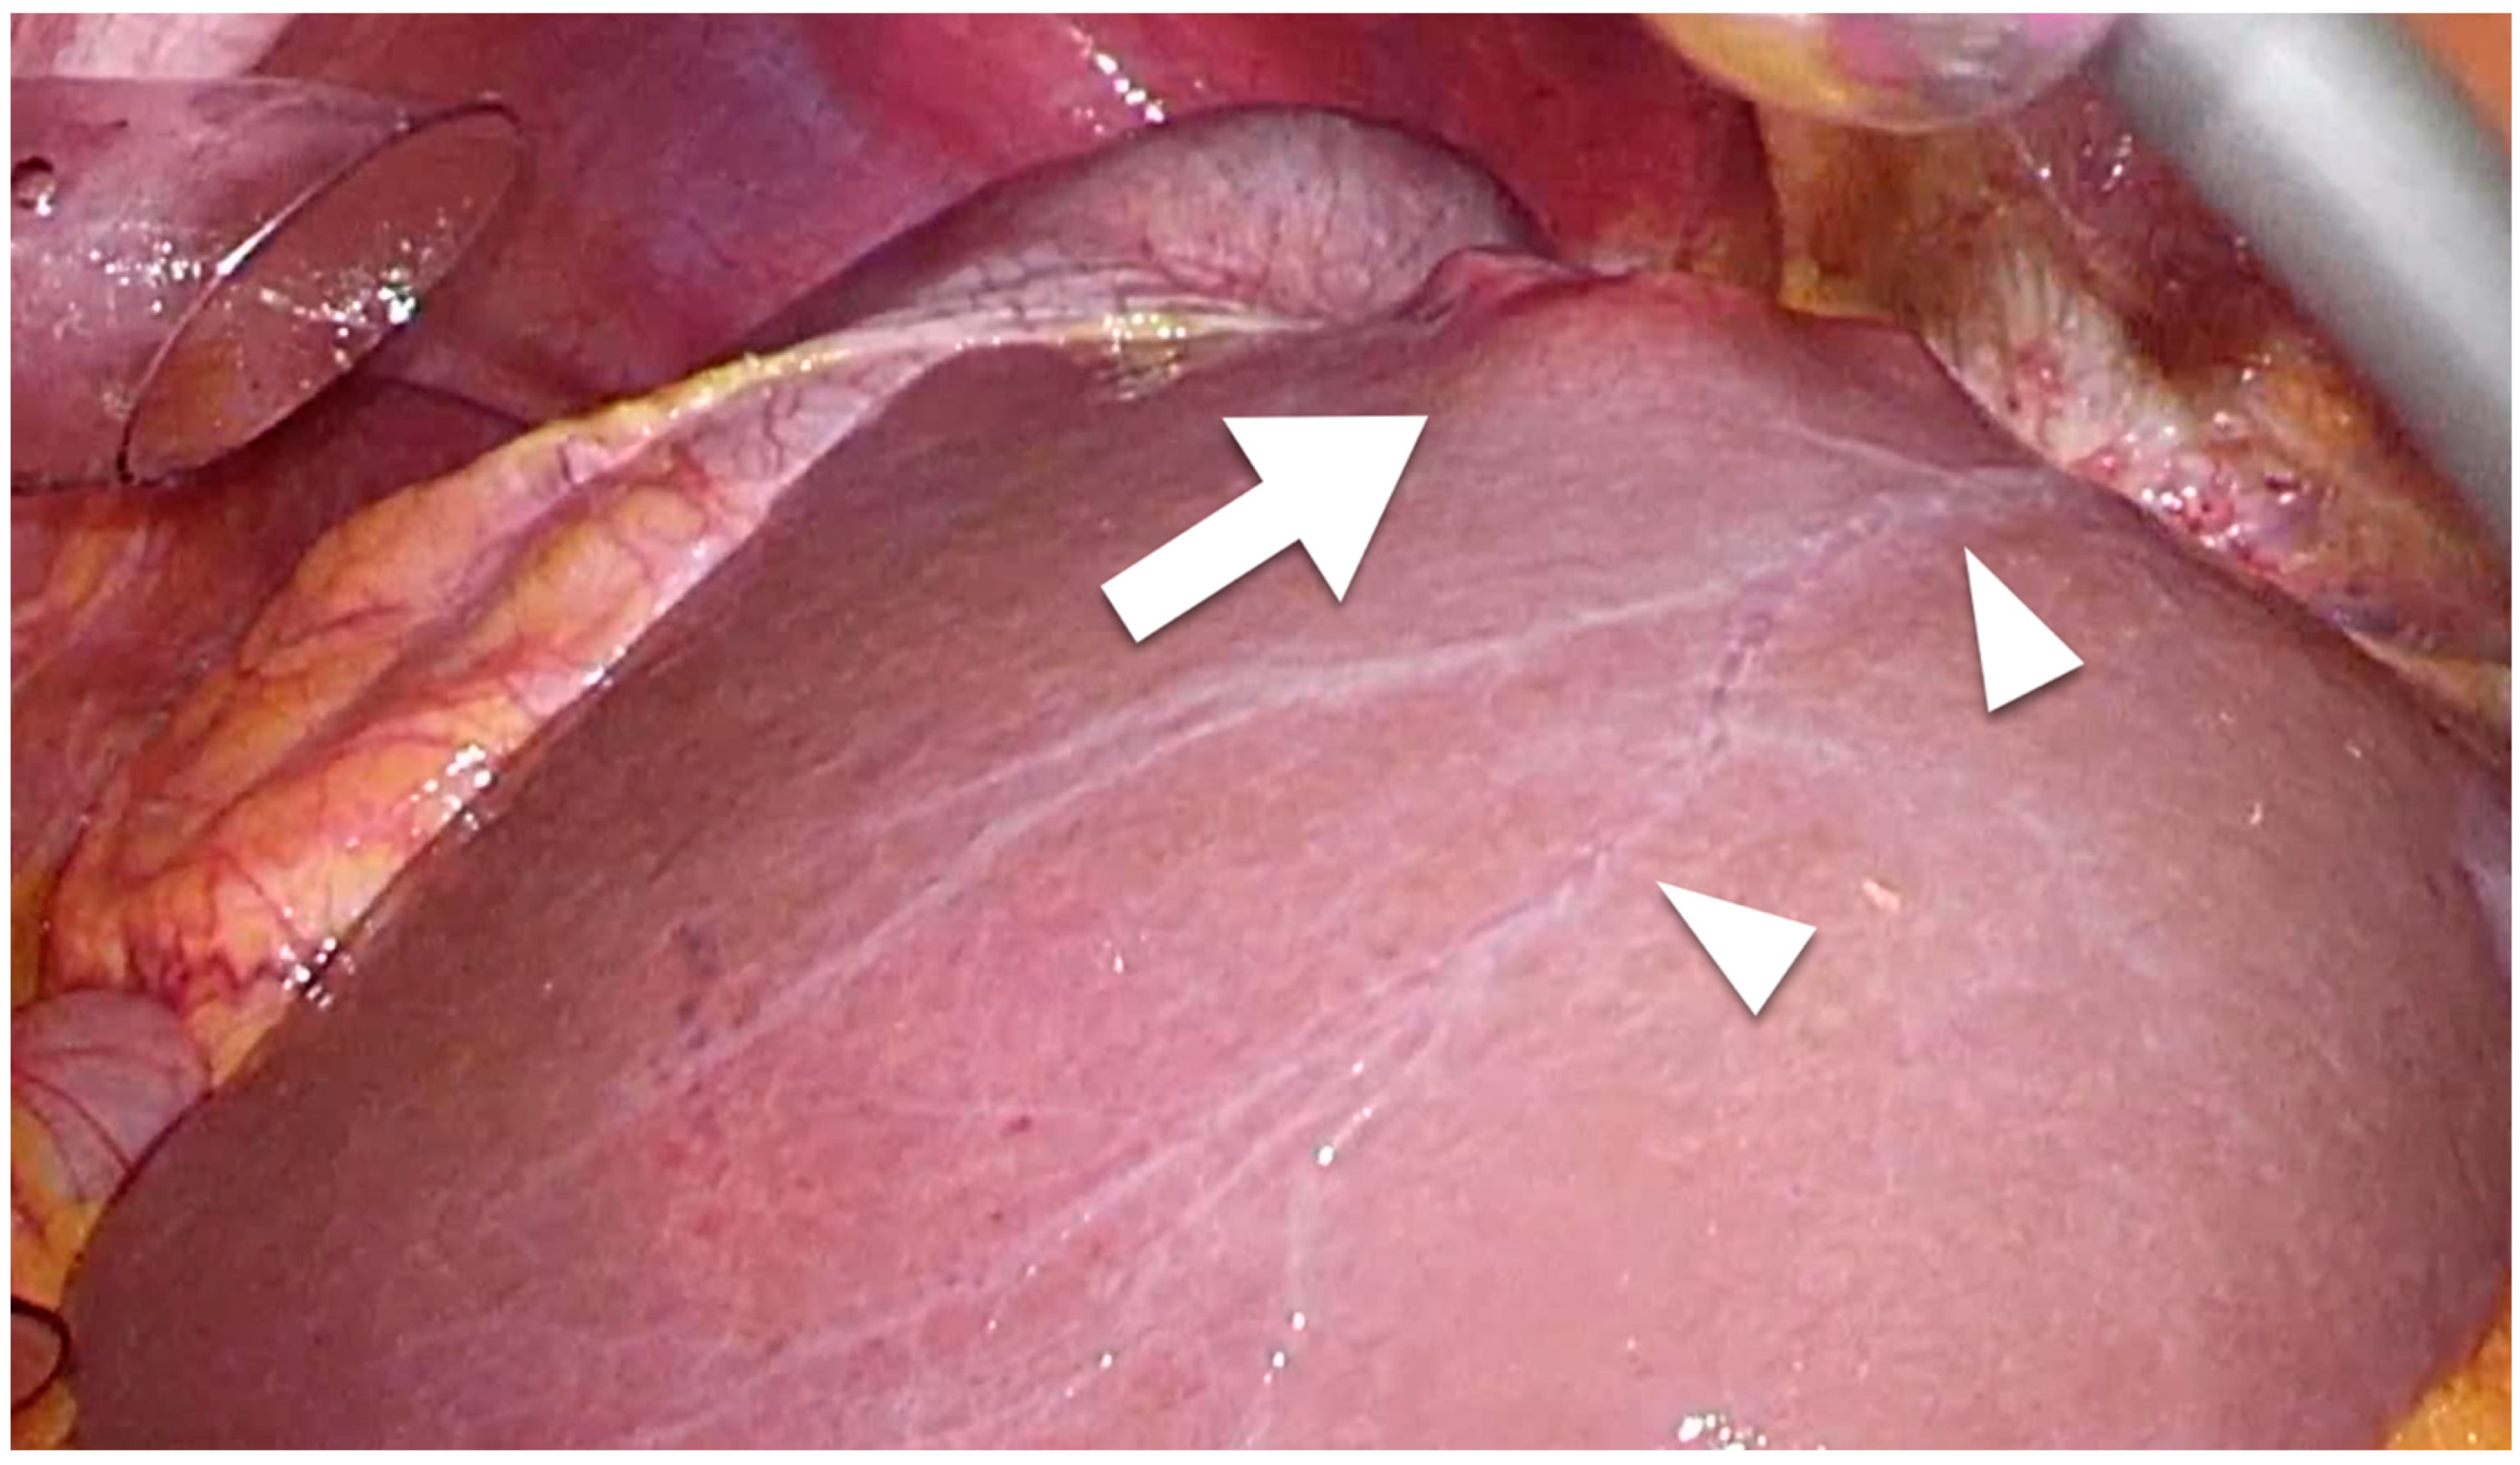

3.1. Intrahepatic Lymphatic Vessels

3.2. Intrahepatic Lymphatic Vessels and Liver Cirrhosis